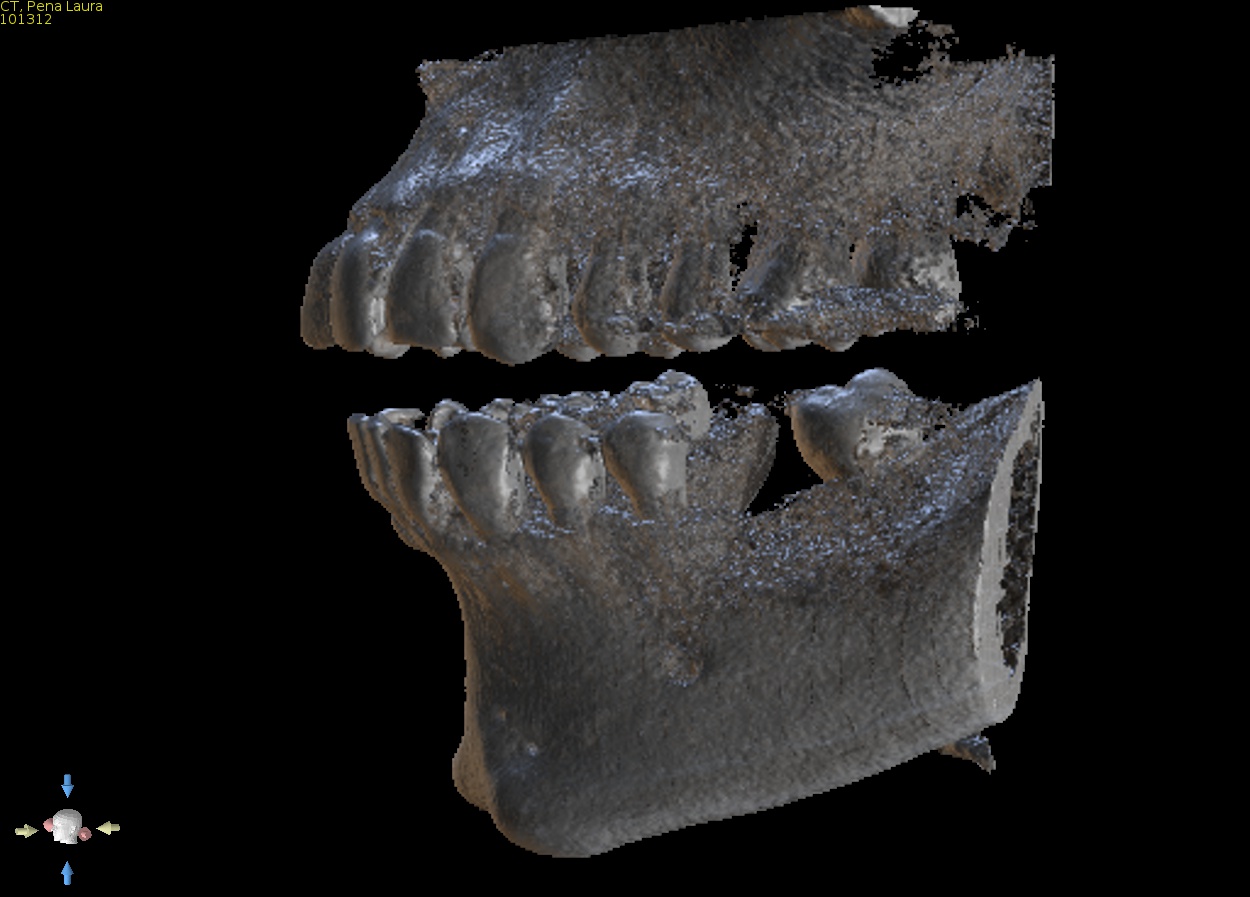

1. CBCT and model merge

Supply a CBCT of the patient and a PVS impression or intra oral scan. We will accurately merge the model with the CBCT so the guide can be made to fit accurately and be tooth and if need be tissue supported. This is a special feature that allows us to offer perfectly fitting guides. Edentulous solutions are also available including tissue or bone supported guides.